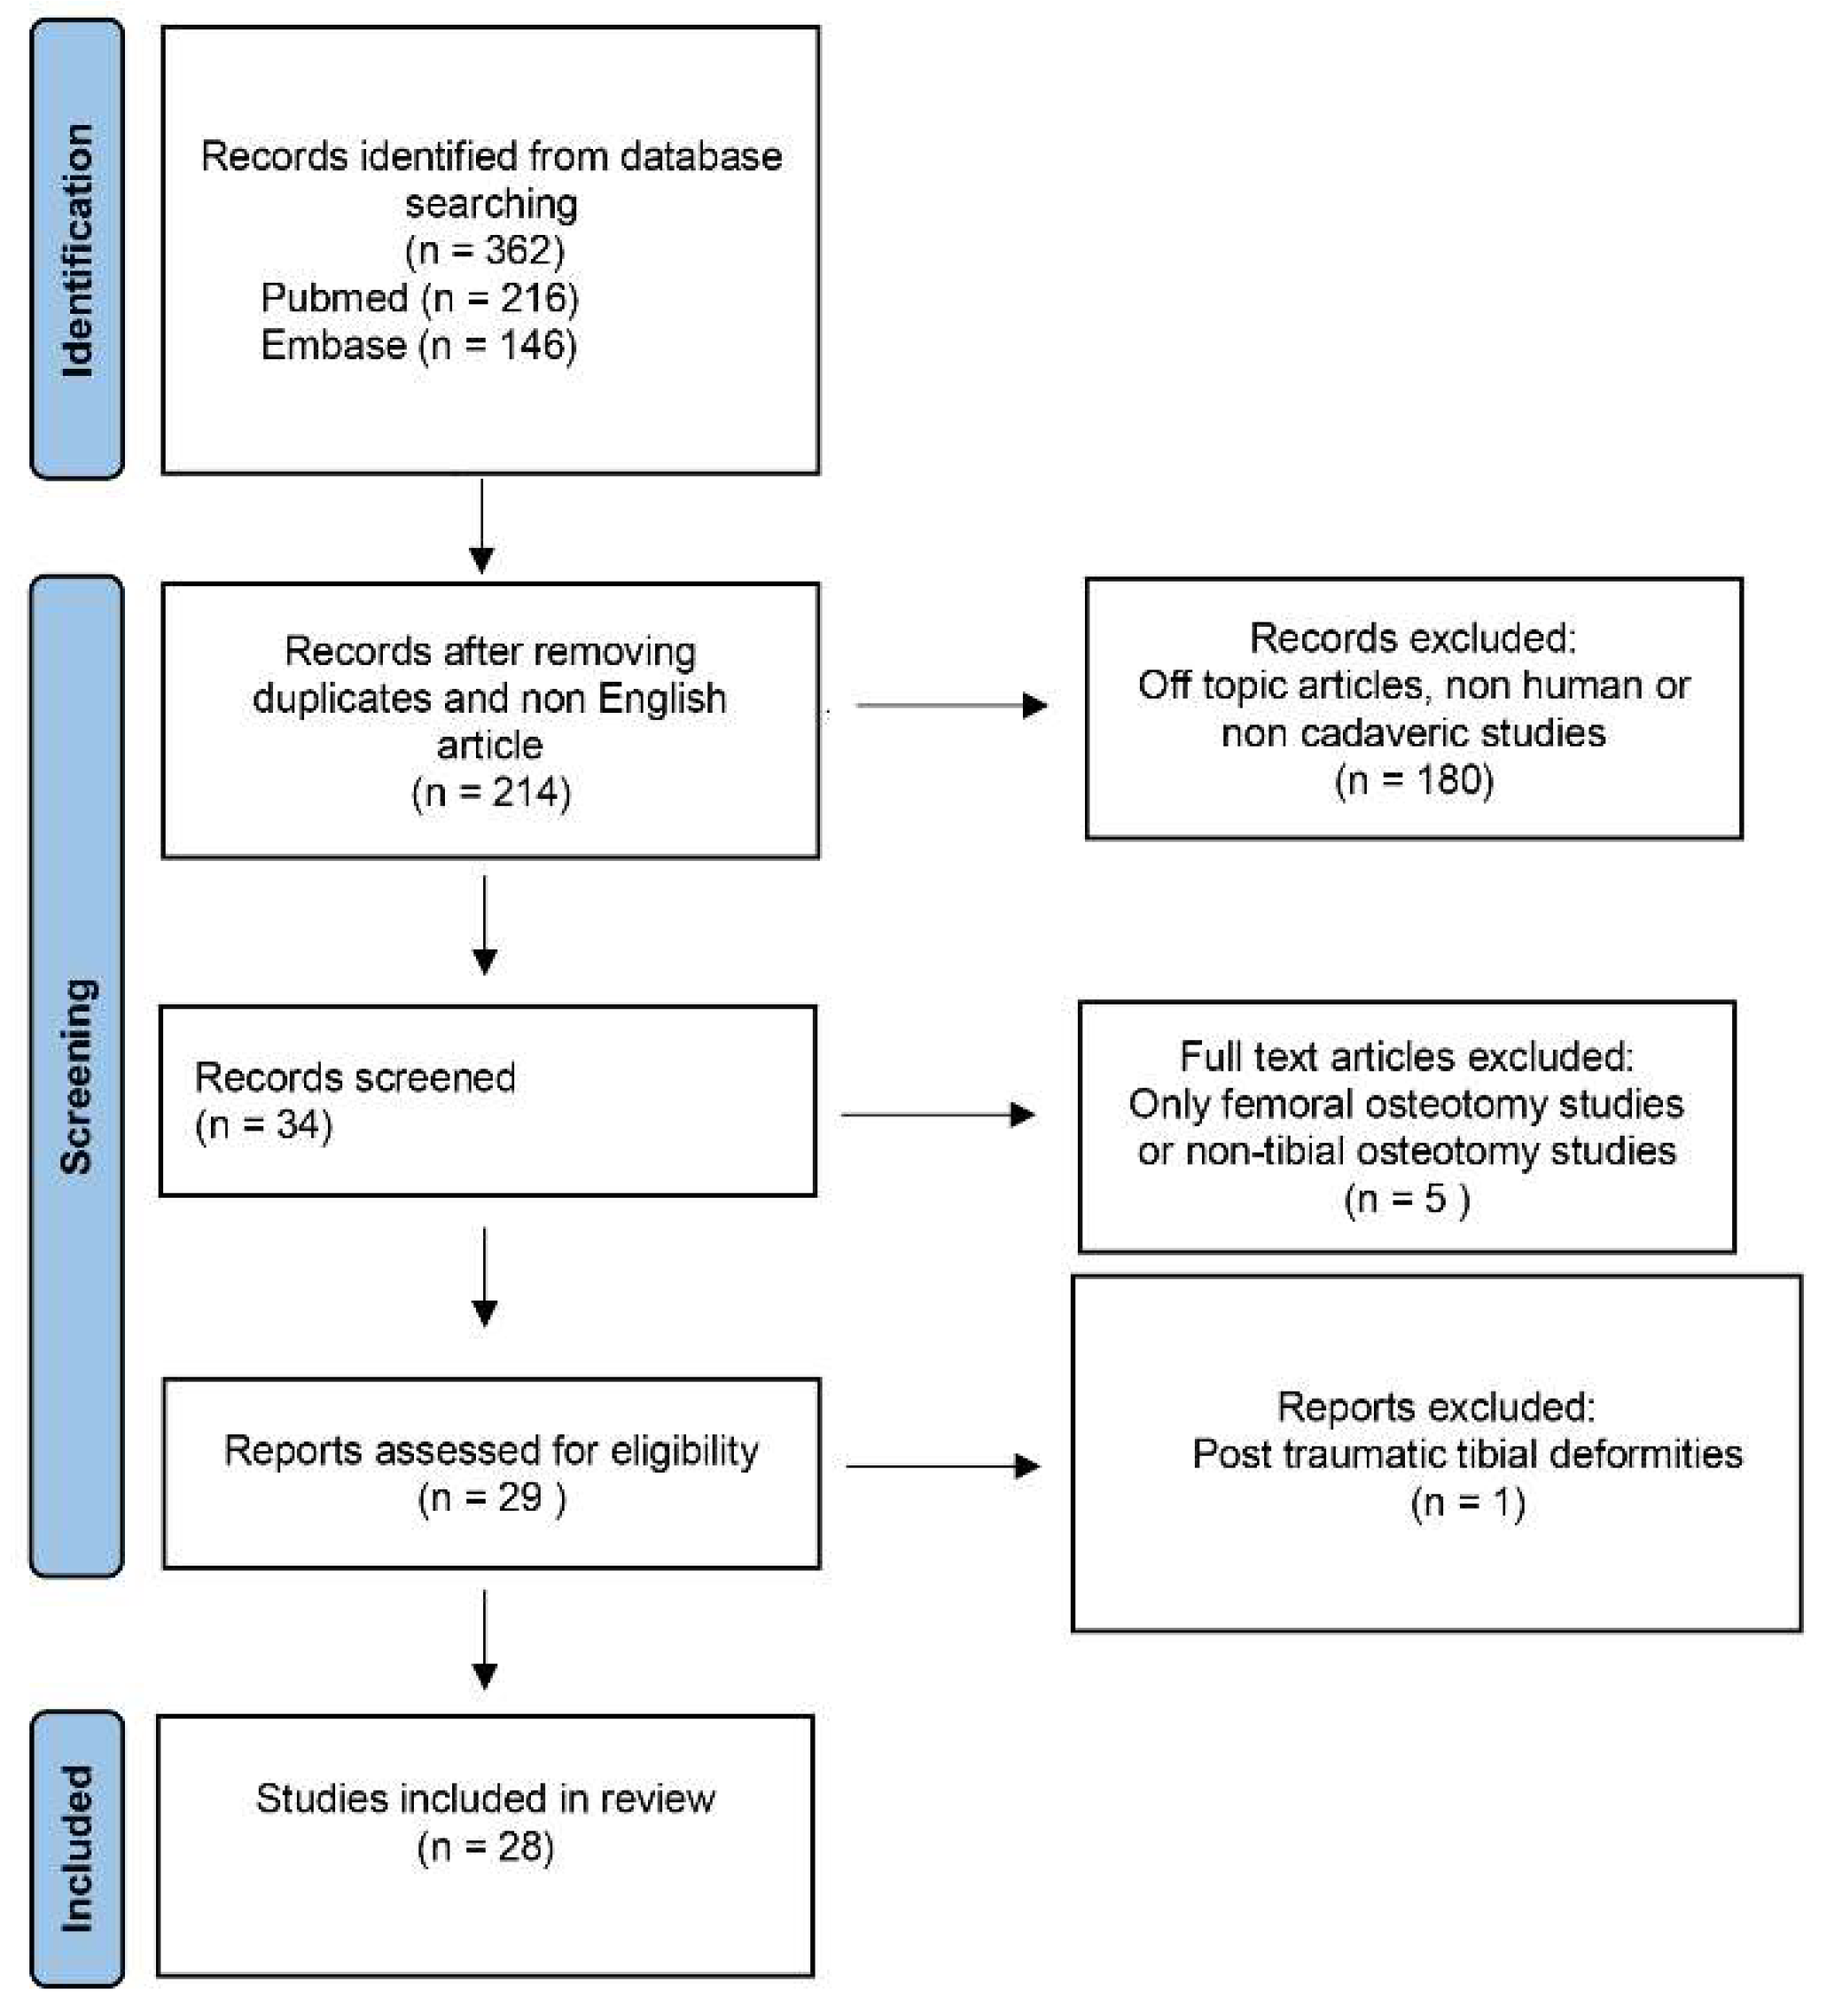

2. Materials and Methods

2.1. Research Strategy

2.2. Study Selection

2.3. Data Extraction and Synthesis